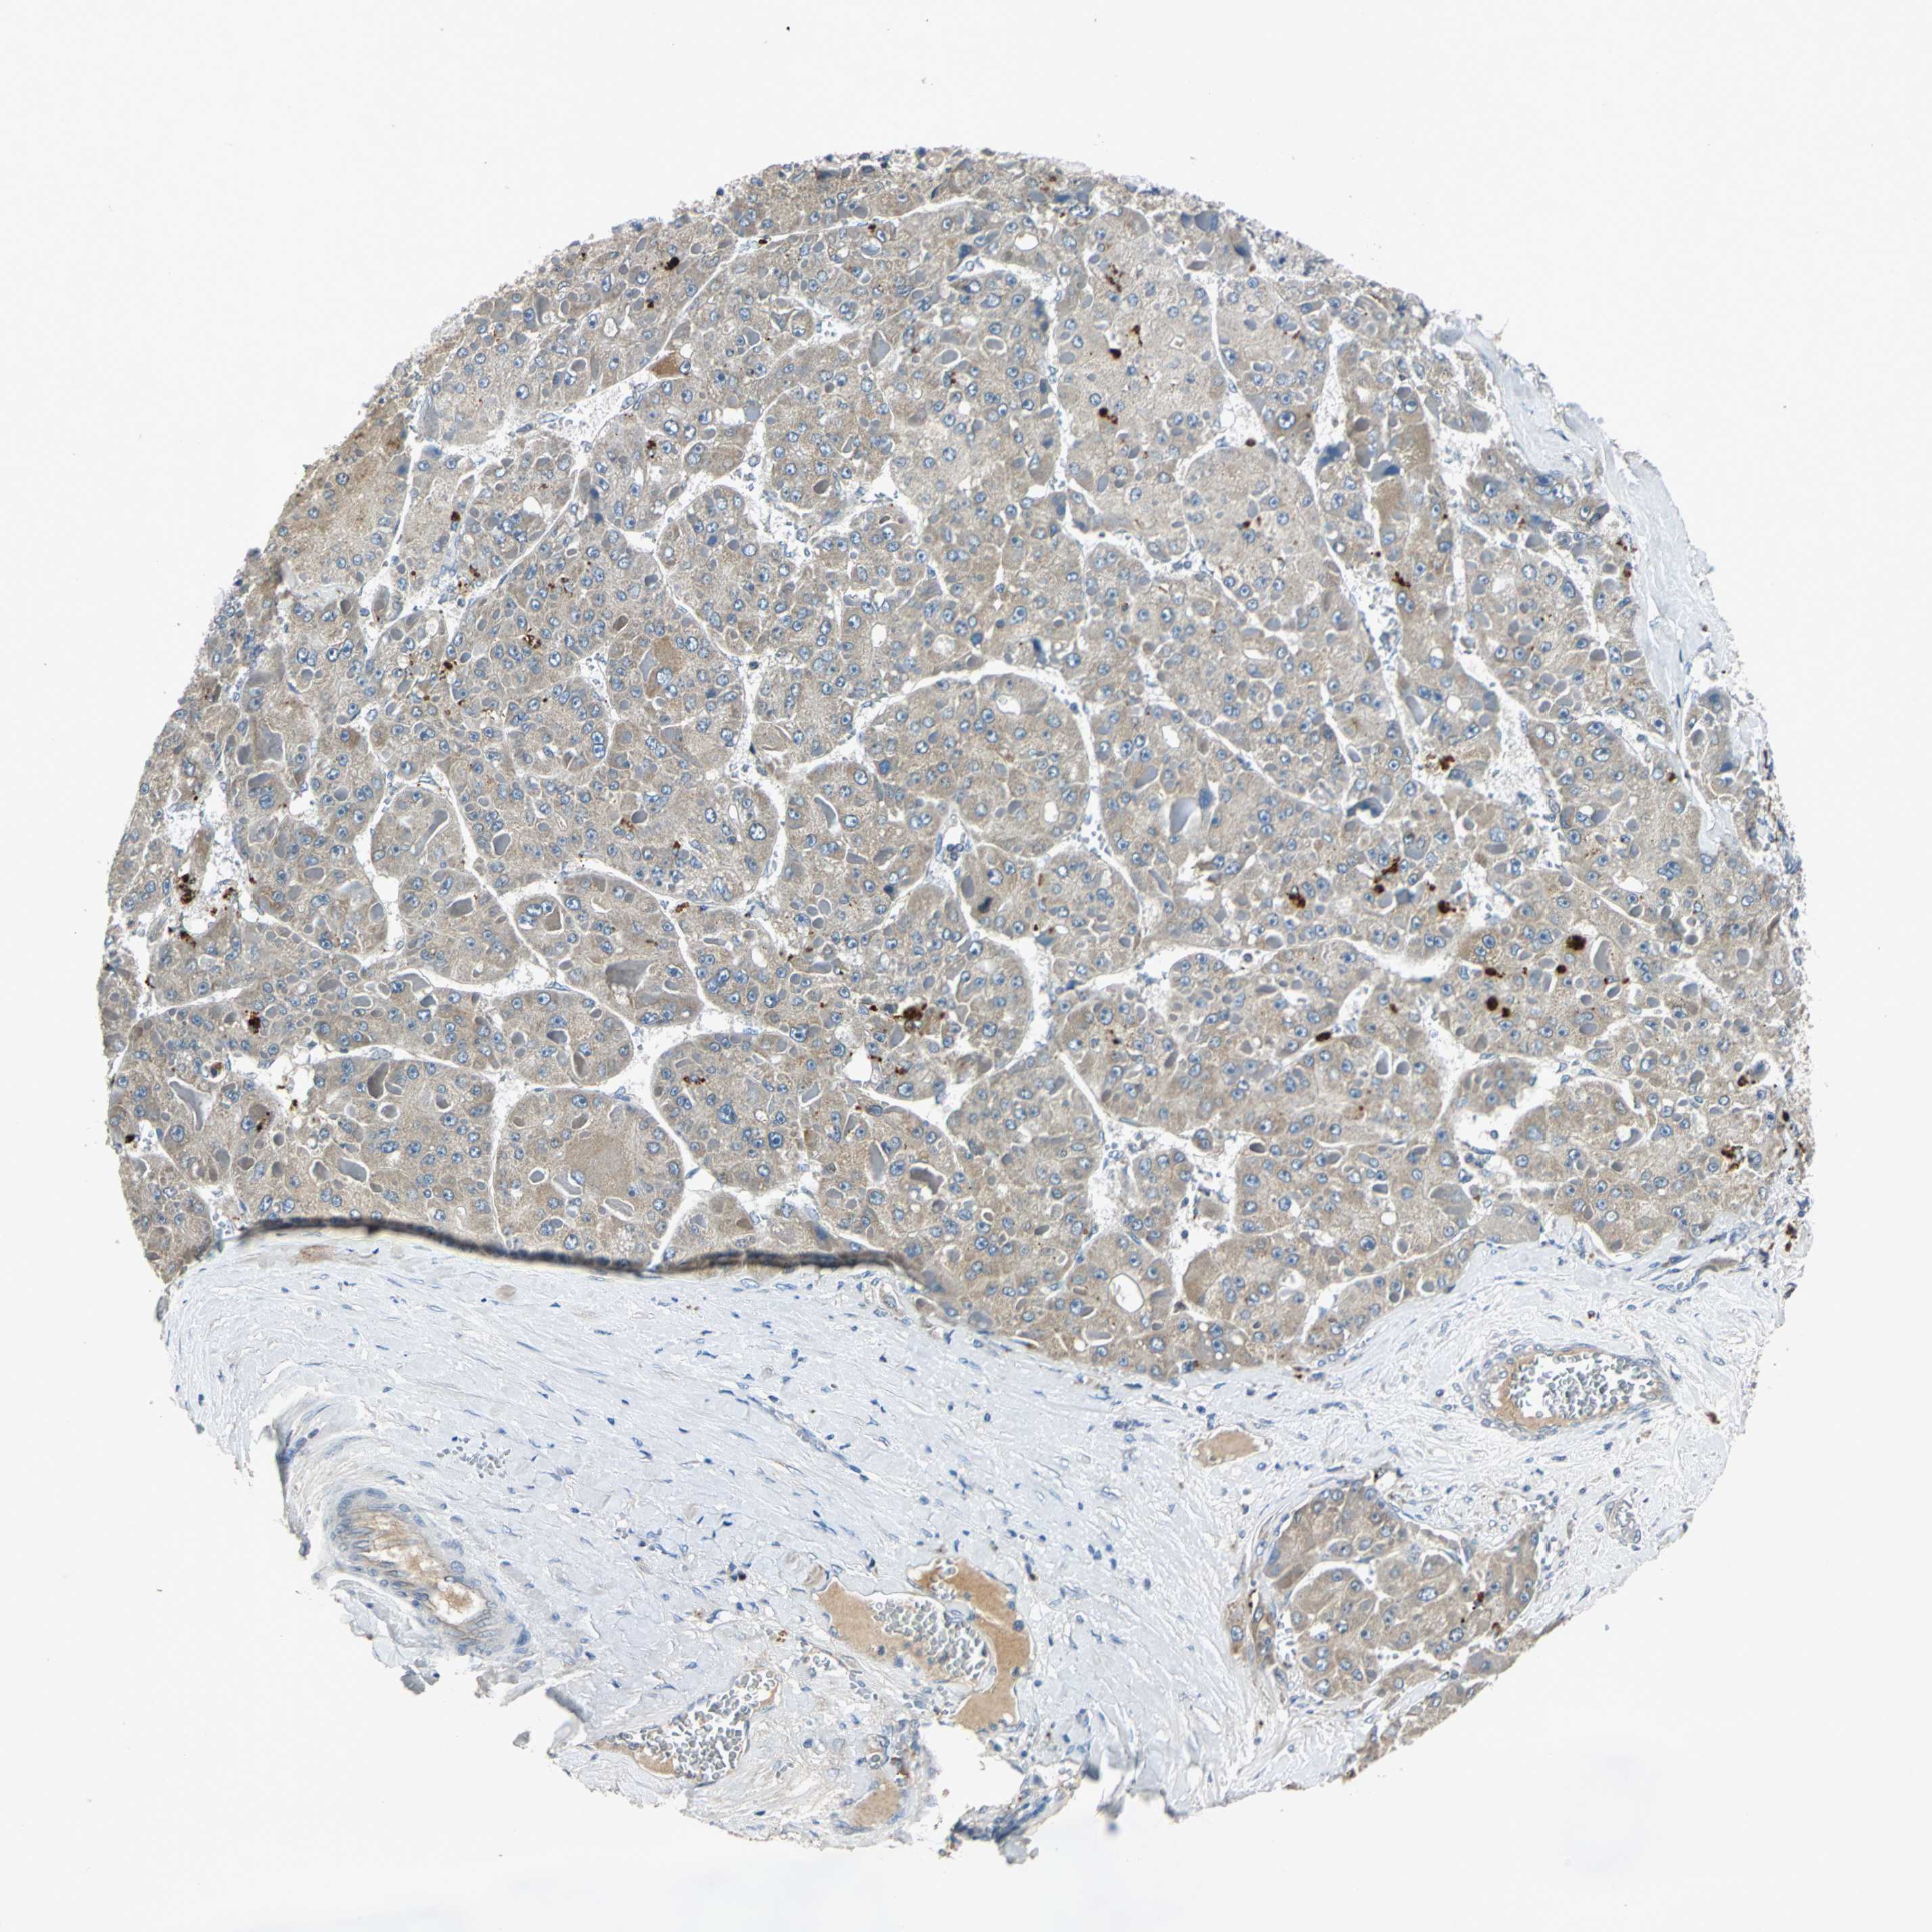

LIVER CANCER - Protein expressioni

A mouse-over function shows sample information and annotation data. Click on an image to view it in a full screen mode. Samples can be filtered based on level of antibody staining by selecting one or several of the following categories: high, medium, low and not detected. The assay and annotation is described here.

Note that samples used for immunohistochemistry by the Human Protein Atlas do not correspond to samples in the TCGA dataset.

Antibody stainingi

Antibody staining in the annotated cell types in the current human tissue is reported as not detected, low, medium, or high, based on conventional immunohistochemistry profiling in selected tissues. This score is based on the combination of the staining intensity and fraction of stained cells.

Each image is clickable and will lead to virtual microscopy that enables deeper exploration of all samples and also displays staining intensity scores, fraction scores and subcellular localization as well as patient and tissue information for each sample.

Antibody HPA006584

Antibody HPA061679

Staining

High

Medium

Low

Not detected

Intensity

Strong

Moderate

Weak

Negative

Quantity

>75%

75%-25%

<25%

None

Location

Nuclear

Cytoplasmic/membranous

Cytoplasmic/membranous,nuclear

Cholangiocarcinoma

Carcinoma, Hepatocellular, NOS